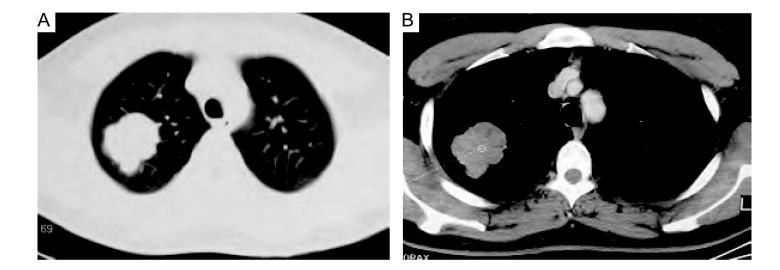

[Well-differentiated fetal adenocarcinoma of lung: a case report with 14 cases literature review].